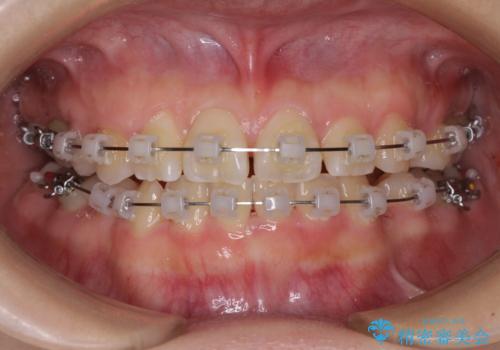

- クリアブラケット

- 2年3ヶ月

親知らずの抜歯により埋もれた奥歯周辺の歯肉が切除され、矯正装置が装着できるようになりました。

奥歯の移動、特に下顎大臼歯の移動は時間がかかることが多く、3年以上の治療期間を想定していましたが、想像以上に動きがよく、2年強で終えることができました。